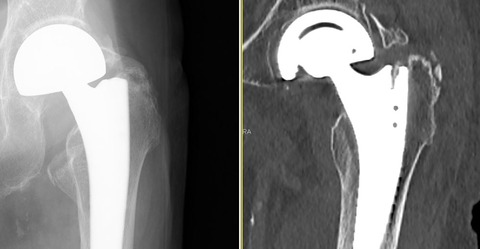

先日、転倒してから左股関節部痛を訴える患者さんが受診されました。大転子部に圧痛があり、明らかに身体所見からは骨折が疑われます。

インプラントがあるので、転位の無いステム周囲骨折(特に大転子部骨折)は診断が難しい症例を散見します。そこで、MRIを撮像してみました。

えっ、人工関節が入っているのにMRIを撮像するの?!という声が上がってきそうです。たしかに、人工関節がハレーションになって、周囲の情報は得られないイメージがあります。

しかし、実際には上記のような画像になります。少し分かりにくいですが、左大転子の骨折もしくは骨挫傷を確認できました。

しかも、インプラントはブラックアウトするだけで、CTのように周囲に線状のハレーションが発生することもありません。

何度かご紹介しているように、私は人工関節後の患者さんにも積極的にMRIを施行しています。人工関節後の感染疑い症例も、関節内に液体が貯留しているか一目瞭然に分かります。

人工関節、脊椎インストゥルメンテーション、骨折手術のプレート、髄内釘であっても、チタン合金であるかぎり、MRIは有用だと思います。